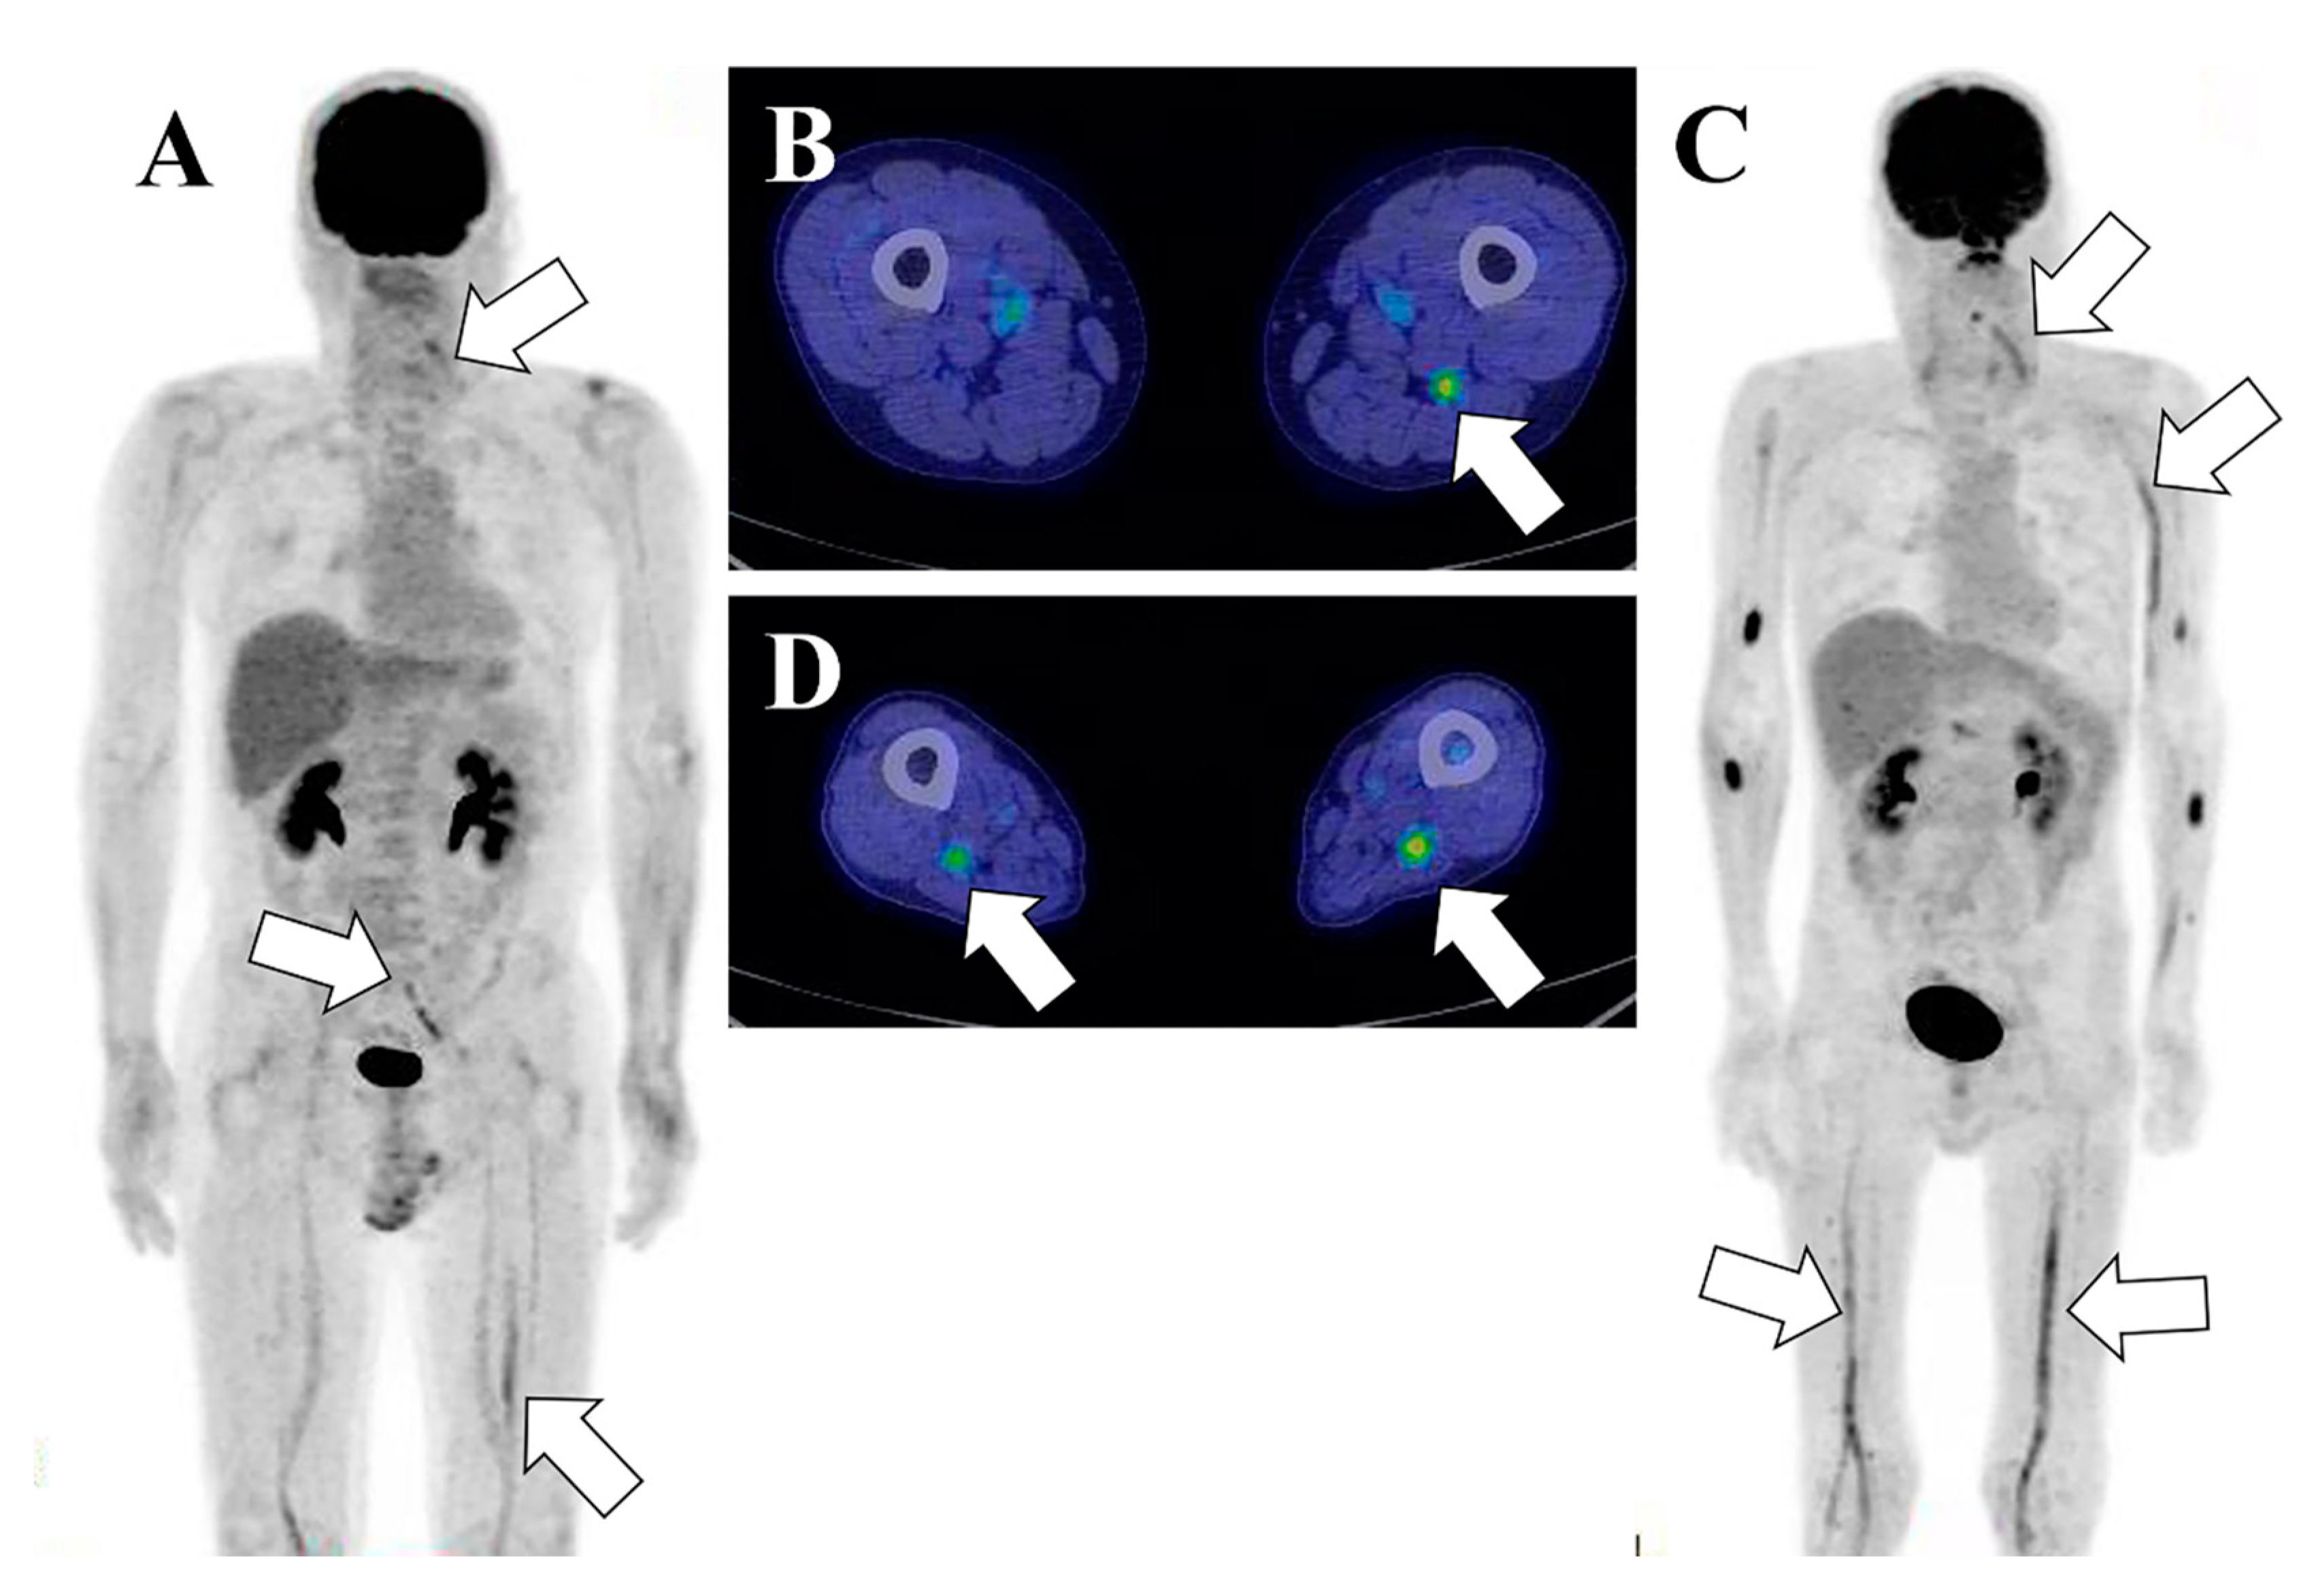

Figure 4.

A 60-year-old male patient with NL who relapsed 2 months later. (A,B). Initial FDG PET/CT image at time of diagnosis. Maximum intensity projection (MIP) image of the FDG PET image demonstrating hypermetabolic lesions in the lumbar plexus, left sciatic nerve, and left cervical spinal nerve 6 (C6) (A). PET/CT fusion image shows a hypermetabolic lesion in the left sciatic nerve (B). (C,D). FDG PET/CT images two months later at the time of NL recurrence. The MIP image shows intense hypermetabolic lesions along bilateral sciatic nerves, left C6 nerve to brachial plexus, and left trigeminal nerve, while the lumber plexus lesion has disappeared. Nodular lesions around the elbow joints are extranodal lesions outside the neural structure (C). PET/CT fusion image shows hypermetabolic lesions in bilateral sciatic nerves (D).